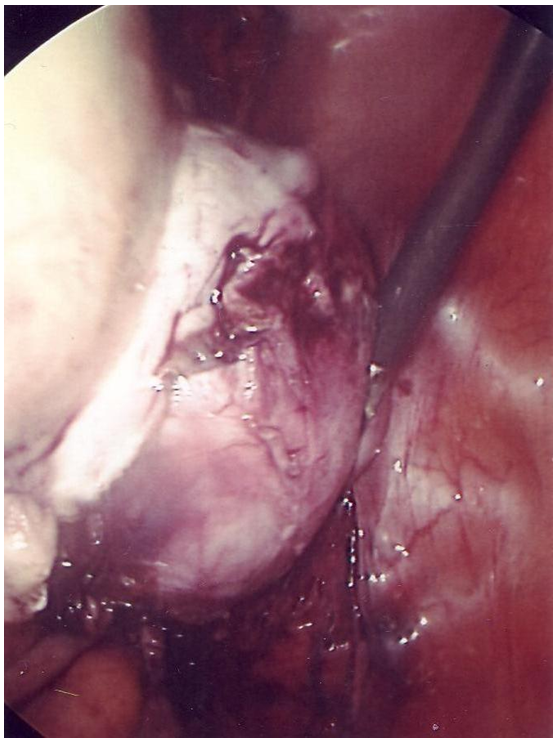

Uterine lipoleiomyoma is a rare benign tumor with an estimated incidence of 0.03% to 0.2% [1]. A 48 year-old, gravida 1 para 1, had a slowly-growing cervical mass. On ultrasound, the mass was around 5 cm in diameter and had fibroid tissue consistency with components of fat consistency (Figure 1 [Fig. 1]). On computed tomography (CT), the tumor appeared encapsulated and measured 6.2×5.2 cm with some areas of what looked like necrosis suggestive of a degenerating fibroid. No adenopathy was detected. The uterus was hypertrophic, sounding to 10 cm, and curettage showed no malignancy. After consultation with the patient, we decided to proceed with total laparoscopic hysterectomy and bilateral salpingo-oophorectomy. Operative findings included a large cervical fibroid that appeared somewhat fleshy and soft in texture (Figure 2 [Fig. 2]). First, the adhesions of the sigmoid colon to the left pelvic sidewall were taken down. The infundibulopelvic ligaments, after visualizing the ureters to be separate from them, were bilaterally coagulated and transected. The broad ligament anterior peritoneum was undermined and transected from round ligament to round ligament. The broad ligament posterior peritoneum was undermined and transected to the level of the uterosacral ligament on each side allowing the ureters to retract laterally away from the uterus, increasing the safety of the procedure. With some trouble, dissection was done to free the bladder from the cervical tumor. The vessels on the left side were then coagulated with bipolar cautery and transected with Harmonic scalpel. The cardinal ligament was taken down with Harmonic scalpel dissection. On the right side, again with difficulty the uterine vessels were skeletonized then coagulated and transected the same way as before. The cardinal ligament on this side was transected the same way. A sponge stick was placed in the anterior vagina and transverse incision was made over it and around the vagina separating it from the cervix. With the help of a tenaculum, the uterus with the cervical mass and adnexa were all removed and passed off. The operation was then continued as usual with uterosacral-cardinal-ligament suspension. Cystoscopy showed indogocarmine coming from both ureteral orifices, excluding ureteral injury. The operation was completed in 68 minutes and blood loss was approximately 150 cc. On opening of the resected tumor, no necrotic areas were noted. Pathological report showed a 258 gram uterus with a lipoleiomyoma that originated in the parametrial soft tissue along the endocervical canal near the lower uterine segment. The maximum dimension of the tumor was 5.5 cm. Incidentally, a 2.1 cm adult granulosa cell tumor was found within the parenchyma of the right ovary.

Figure 2: Laparoscopic view of the large cervical mass